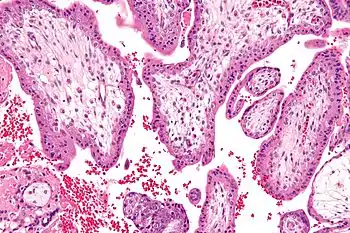

Micrograph showing chorionic villi—the tissue that is collected in CVS. H&E stain.

Chorionic villus sampling (CVS), sometimes called "chorionic villous sampling" (as "villous" is the adjectival form of the word "villus"),[1] is a form of prenatal diagnosis done to determine chromosomal or genetic disorders in the fetus. It entails sampling of the chorionic villus (placental tissue) and testing it for chromosomal abnormalities, usually with FISH or PCR. CVS usually takes place at 10–12 weeks' gestation, earlier than amniocentesis or percutaneous umbilical cord blood sampling. It is the preferred technique before 15 weeks.[2][3]